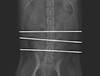

교통사고를 당해 척추가 부러진 고양이 작성자 한수 작성시간 15.09.07 조회수 97

교통사고를 당해 척추가 부러진 고양이 작성자 옥상... 작성시간 15.09.06 조회수 414